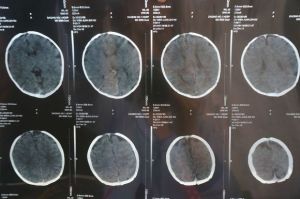

腦CT 2、腦CT可明確顯示顱內腫瘤的數目、部位、大小、輪廓、密度、瘤內出血、鈣化以及擴散程度。

4、腦CT對顱腦損傷可分辨血腫的大小、形態、範圍、數目及其鄰近腦組織壓迫情況。觀察有無亞急性或慢性顱內血腫的存在,判斷顱腦損傷的吸收、縮小情況,亦可顯示腦軟化、腦萎縮、腦積水及腦穿通畸形等後遺症。